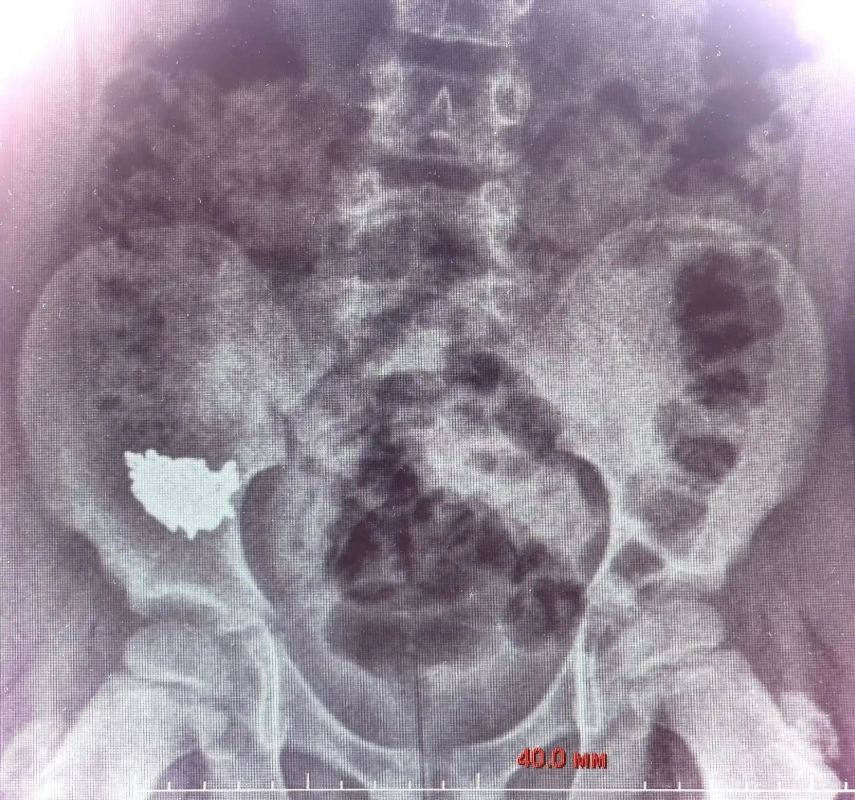

Врачи сделали рентген и узнали, что цепочка расположилась внизу живота, в правой подвздошной области. Ребёнка госпитализировали.

Спустя четверо суток снимки показали, что украшение не двигается по ЖКТ. Тогда врачи решили достать цепочку с помощью операции, так как существовал риск перфорации кишки и перитонита.